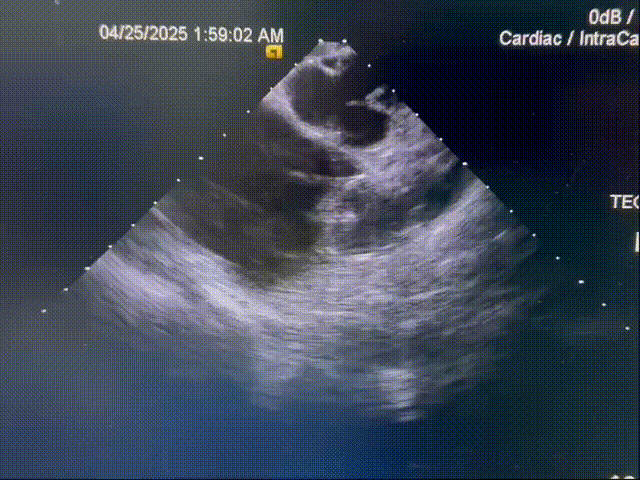

释放后再造影

释放钢缆后造影,封堵器位置稳定,释放后形态良好

超声确认

封堵器位置良好,术后无心包积液